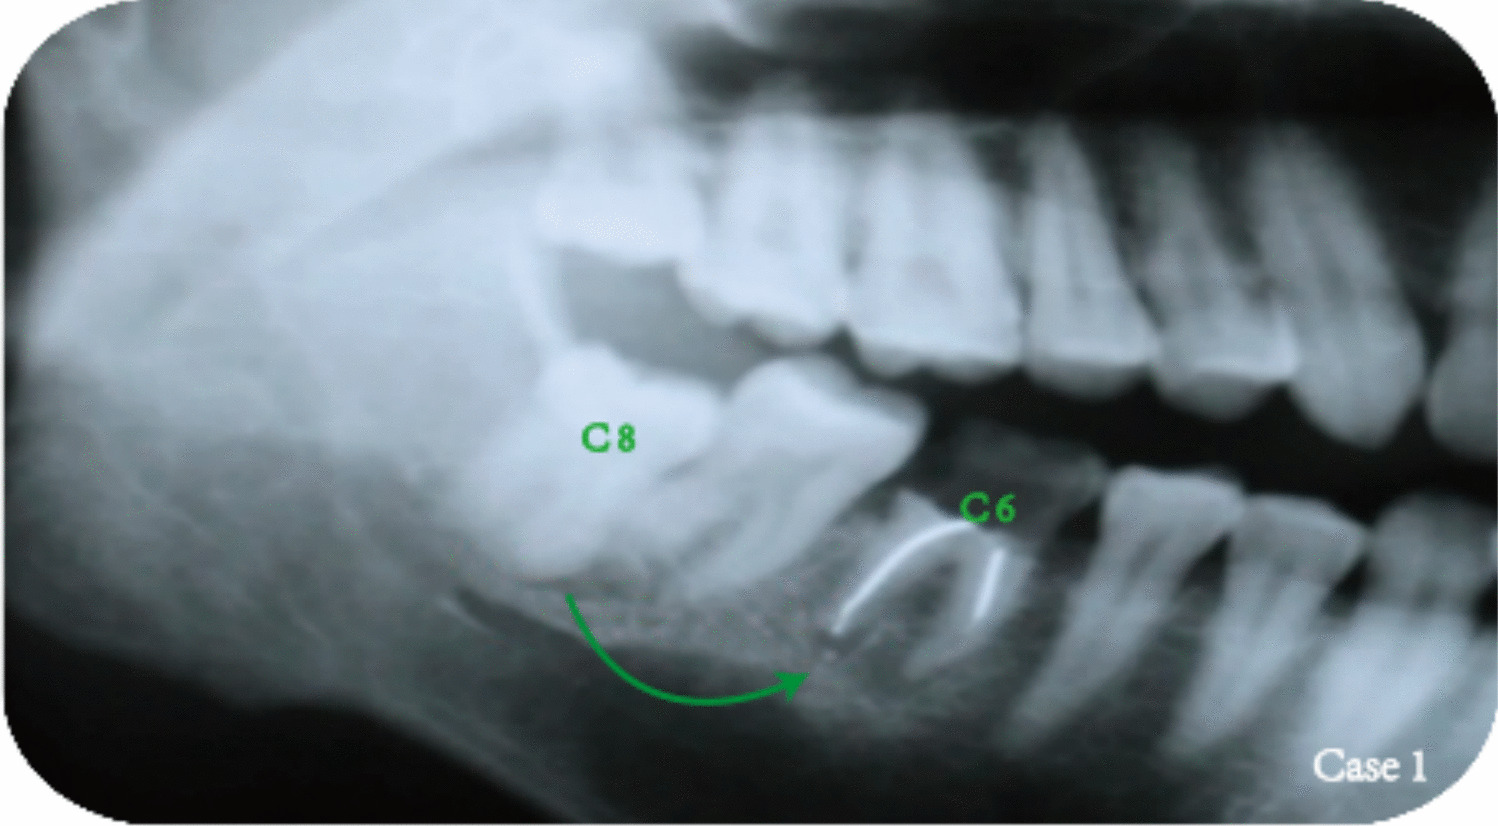

The patient, a 32-year-old male, presented to the Oral-Dental Surgery Department at Peking Union Medical College Hospital in June 1997 due to recurrent pain in the lower right molar region. Clinical and radiographic examinations revealed a residual crown with a periodontal shadow following RCT of tooth 46, as well as impaction of the lower right third molar (tooth 48) (Fig. 10). Despite undergoing RCT, tooth 46 was diagnosed with chronic apical infection and deemed to have a poor prognosis. Given that the root size of tooth 48 was comparable to that of the alveolus of tooth 46 and considering its fused roots facilitated extraction, posterior tooth autotransplantation was proposed. The treatment plan involved extracting the residual crown of tooth 46, followed by transplantation of tooth 48 into the alveolus previously occupied by tooth 46; endodontic treatment would be performed subsequently.

Fig. 10

Preoperative panoramic radiograph and the treatment planning